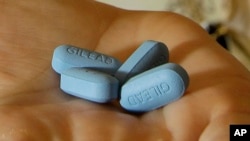

Pusat Pengawasan dan Pencegahan Penyakit Amerika (CDC) mengungkapkan bahwa metode PrEP (Pe-exposure prophylaxis), yang berbentuk pil, adalah cara yang efektif untuk mencegah orang berisiko tetapi berstatus HIV negatif, dari infeksi HIV.

Pil bermerk Truvada ini sebenarnya adalah salah satu obat yang digunakan untuk mengobati orang yang sudah positif HIV.

Namun, jika dikonsumsi setiap hari oleh orang yang berisiko (pengguna jarum suntik, orang yang punya banyak pasangan seksual, pekerja seks komersial) dan berstatus HIV negatif, maka saat dia terekspos HIV, obat ini akan membuat HIV berhenti berlipatganda dan tidak bisa menginfeksi tubuh.

CDC menyebut, jika dikonsumsi setiap hari, PrEP efektif mencegah HIV hingga 92%.

Meskipun begitu, PrEP tidak mencegah penularan penyakit menular seksual lainnya.

Di Amerika Serikat, harga awal obat ini mencapai US$1300 (Rp19 juta) per botolnya (untuk 30 hari).

Namun, mayoritas asuransi di Amerika membantu biaya pembelian PrEP.

Bahkan bagi mereka yang memiliki asuransi Medicaid atau Medicare, hanya perlu mengeluarkan sekitar US$8 (Rp120.000) per botolnya.

Sementara untuk asuransi lainnya, pengguna ‘hanya’ merogoh kocek rata-rata US$40 (Rp600.000) per botol.

Meskipun sudah masuk dalam rekomendasi Badan Kesehatan Dunia (WHO) sebagai pencegah HIV, metode PrEP belum diterapkan di Indonesia.

Banyak dari mereka yang ingin mengikuti metode ini memilih untuk mendapatkan PrEP dari Thailand, meskipun dalam bentuk obat generik, sehingga harganya lebih murah, yaitu sekitar Rp250.000 per botol.

Kementerian Kesehatan Indonesia mengungkapkan masalah utama penyediaan PrEP di Indonesia adalah soal dana.

Pemerintah Indonesia setiap tahunnya dibantu dana dari Global Fund sebesar Rp800 miliar, untuk menyediakan obat antiretroviral bagi mereka yang HIV positif. “Sehingga orang yang positif HIV dapat obat gratis”.

Tapi kalau PrEP juga diterapkan di Indonesia, “duitnya rasanya berat,” kata Direktur Pencegahan dan Pengendalian Penyakit Menular Langsung Kementerian Kesehatan Wiendra Waworuntu. (rh)